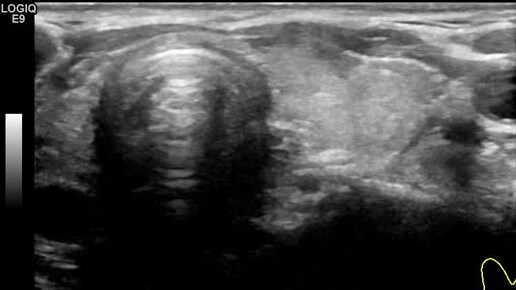

Видео к статье "Стратификация узлов щитовидной железы. TI-RADS-3" https://dzen.ru/a/Zv4svErHVi-eImKZ

Ультразвуковые находки от врача УЗД Зорина Я.П.